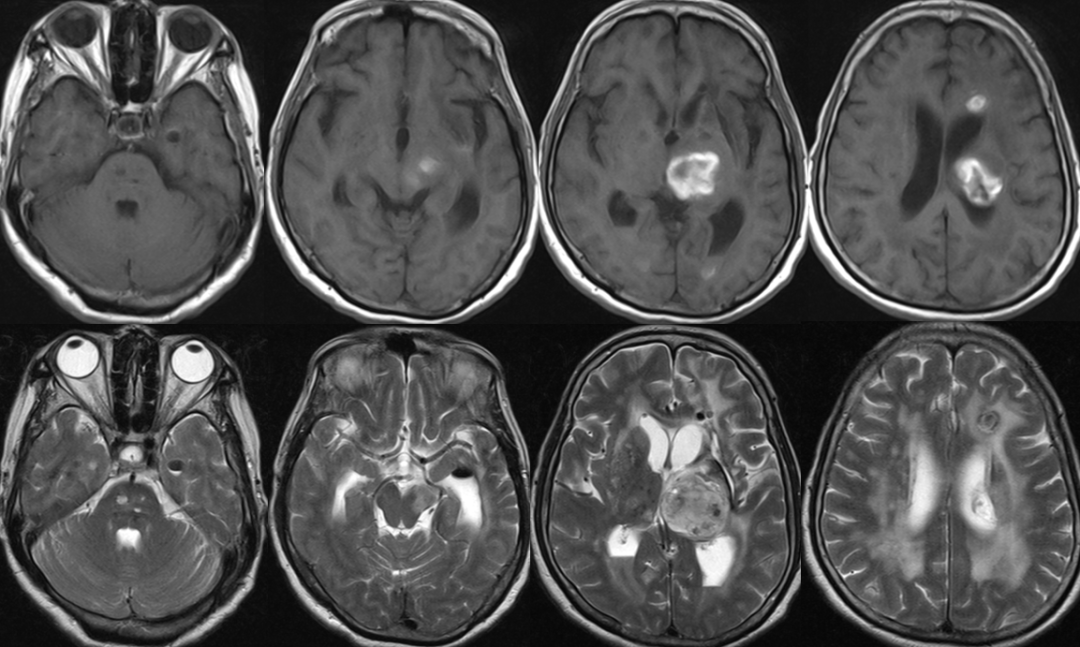

2014-11-18 0am CT

2014-11-18 10am CT

2014-11-19 CT

2014-11-20 CT

2014-11-24 CT

2014-11-18 CT

2014-11-27 CT

2014-12-2 CT